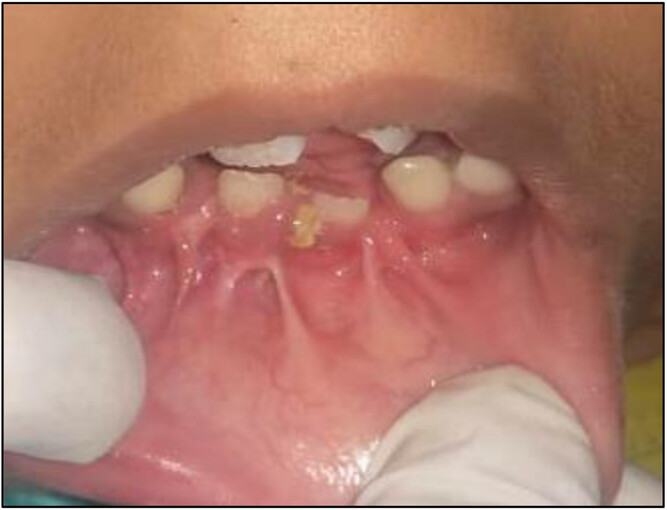

- Hypodontia: A significant proportion of individuals with OFDS exhibit hypodontia, specifically involving the lateral incisors.

- Supernumerary Teeth: These are extra teeth that can erupt in conjunction with the regular set, leading to crowding and misalignment.

- Delayed Eruption: Delays in the eruption of teeth can also be symptomatic, necessitating continuous dental monitoring.